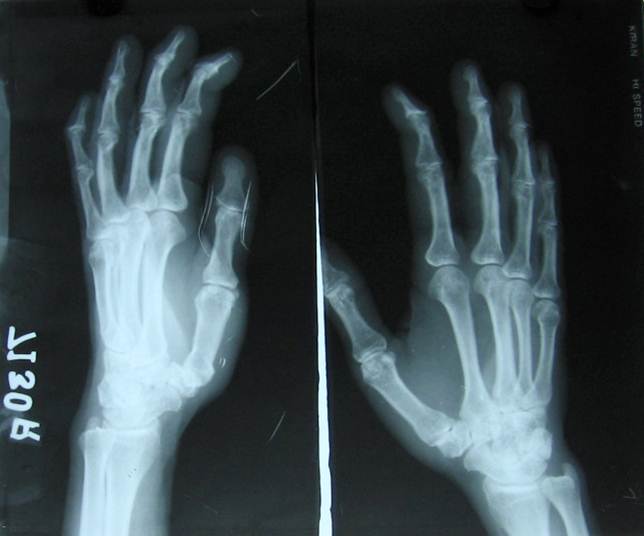

PSORIATRIC ARTHRITIS4